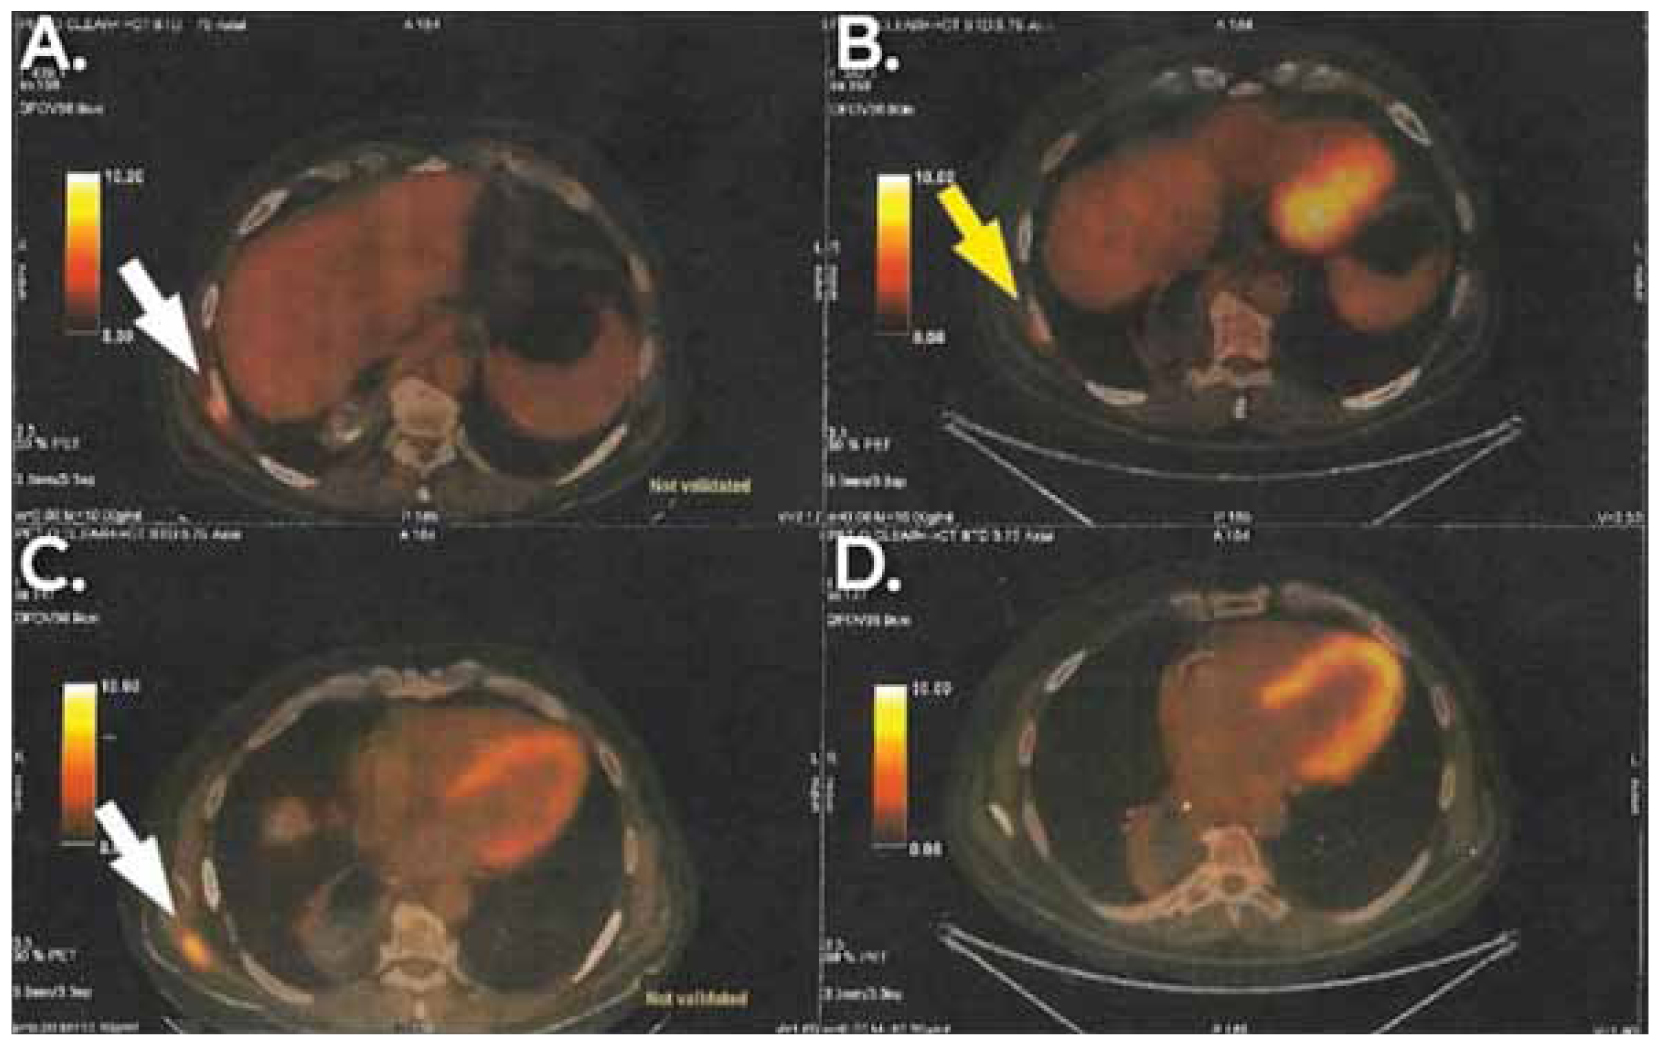

Targeted chemotherapy for the neuroendocrine component of the tumour was added, consisting of three cycles of carboplatin and etoposide. A few months later, a routine follow-up PET/CT scan revealed an enlarged lymph node at the left paraaortic space (5,4 x 3,6 cm and SUVmax: 10.8), an enlarged lymph node behind head of the pancreas (1 x 0,8 cm and SUVmax: 3,2) and a high 18F-FDG uptake nodular lesion at the left posterolateral thoracic wall (0,9 x 0,4 cm and SUVmax: 3,3). Following multidisciplinary meeting and multimodal decision-making, cisplatin, pembrolizumab and herceptin were administered. A second PET/CT scan was performed a few weeks later and confirmed that the metastatic lesions had exhibited no progression. At the same time, a new metastasis was identified in the right latissimus dorsi (2,7 x 1,8 cm and SUVmax: 8,1). The figures below depict the differences between the first and the second PET/CT scan that were done post-operatively (Figures 3,4).

Figure 3. PET/CT showing the findings after the first and the second schemes of adjuvant therapy and their relapses, respectively (B and D show the first relapse and A and C show the second relapse). Enlarged paraaortic lymph nodes and a mass in the lumen of the right colic flexure(big and small yellow arrow in B) and enlarged lymph nodes behind the margin of the head and body of the pancreas (big yellow arrow in D) were findings of the first relapse. Further enlarged paraaortic lymph nodes with higher SUVmax(big white arrow in A) and further enlarged posterior pancreatic lymph nodes, behind the margin of the head and body of the pancreas, (big white arrow in C) were findings of the second relapse.

Figure 4. PET/CT showing the findings after the first and the second schemes of adjuvant therapy and their relapses respectively(B and D show the first relapse and A and C show the second relapse). Subcutaneous mass in the lateral and posterior thoracic wall (big yellow arrow in B) was the finding of the first relapse. An even larger subcutaneous mass in the lateral and posterior thoracic wall (white arrow in A) and an independent mass in the posterior thoracic wall in contact with latissimus dorsi (white arrow in C, absent in D) were the findings of the second relapse.